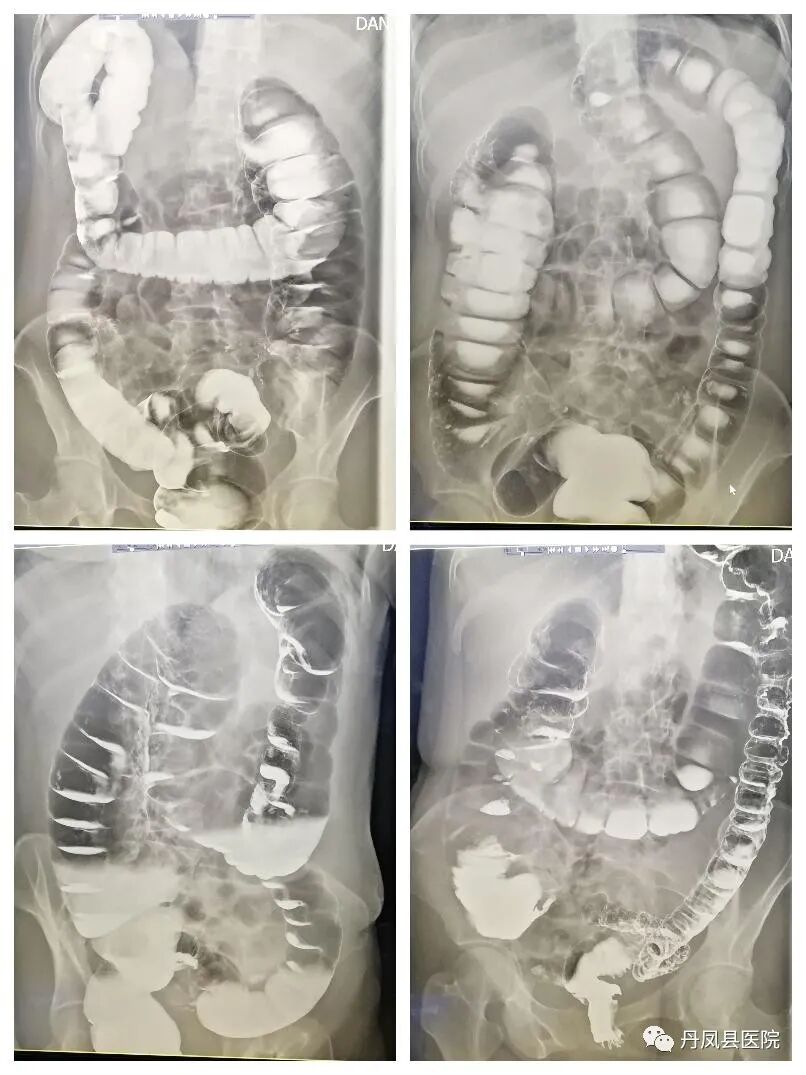

![结肠造影.jpg]()

结肠气钡双重造影